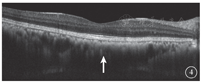

患者女,51岁,因左眼视力下降6年于2018年1月15日到吉林大学第二医院眼科就诊。否认相关既往史及家族史。患者颜面部及上肢可见多个神经纤维瘤及咖啡斑(图1)。眼科检查:右眼、左眼矫正视力分别为1.0、0.15。双眼虹膜见Lisch结节(图2),其余眼前节正常。眼底彩色照相、FAF及FFA检查,双眼均未见异常。红外眼底成像检查,双眼后极部多发片状强反射病灶(图3)。OCT增强深度成像(EDI-OCT)检查,与红外眼底成像强反射病灶对应处脉络膜毛细血管层反射增强(图4)。ICGA检查,早期可见与红外眼底成像强反射病灶相对应处呈弱荧光,随着时间延长,中晚期弱荧光面积逐渐缩小直至消失(图5)。诊断:Ⅰ型神经纤维瘤病。

Ⅰ型神经纤维瘤病大多存在脉络膜结节,常规眼底检查和眼底彩色照相不能发现病变[5]。本文例2患者仅在彩色眼底像中可见双眼黄斑区末梢血管略扭曲,这样的异常血管只存在于视网膜浅层,常见于颞上、颞下静脉的二三级分支,且在FFA上无荧光素渗漏;在EDI-OCT上可见对应位置的脉络膜毛细血管层萎缩以及脉络膜大血管缺失。但脉络膜大血管在解剖结构上是缺失还是仅仅被压缩,尚无定论。对于这样的脉络膜结节,最有效的检查手段是红外眼底成像。这些脉络膜结节由包绕神经纤维轴突增生的施万细胞和黑色素细胞组成,由于黑色素细胞对红外线的反向散射作用,病灶在红外眼底成像上表现为强反射。另外,脉络膜结节的致密结构降低了可吸收红外线的血红蛋白和水等血液成分的含量,病变区域红外线吸收得相对减少也是红外眼底成像上反射增强的原因之一[6]。